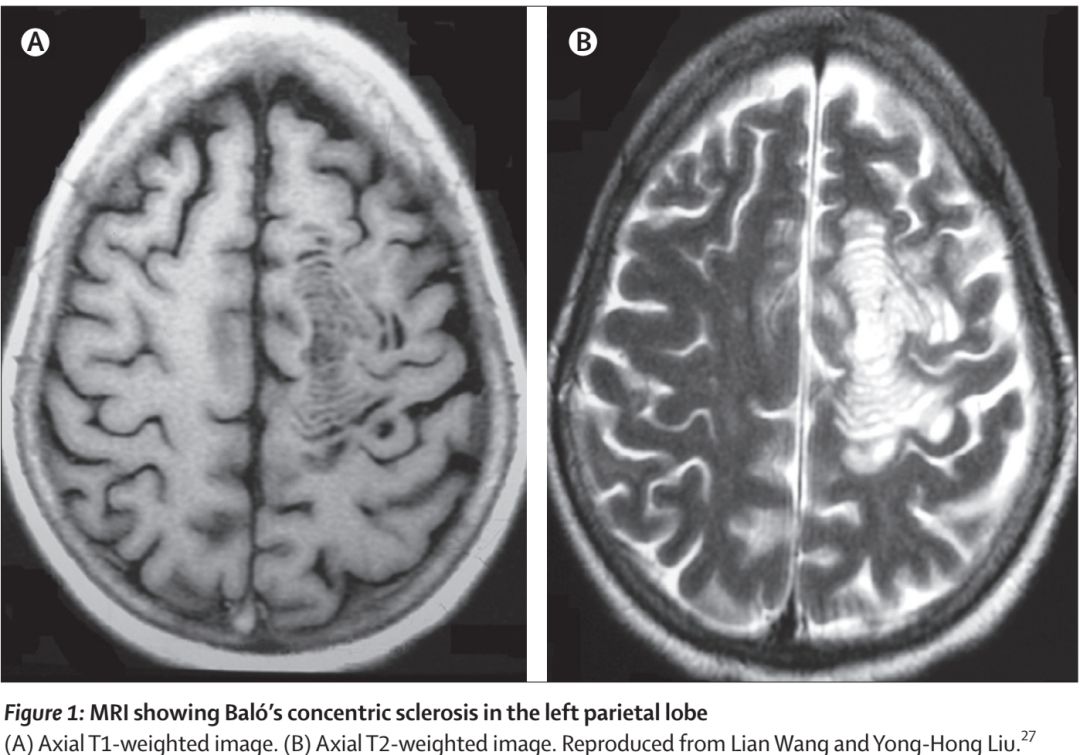

MRI表现:Baló’s 在T1像的特点是多个等、低信号交替的同心圆,在T2加权序列上表现为围绕高信号圆心(风暴眼)的高低信号环,也有其他模式如玫瑰、康乃馨甚至马赛克形状的报道。

最经典的,年轮样改变,数不清多少环长这样:

图自:Lancet Neurol 2014; 13: 740–46